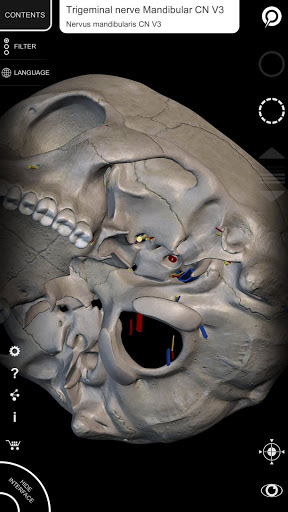

"Anatomy 3D Atlas" cho phép bạn nghiên cứu giải phẫu người theo cách dễ dàng và tương tác.

Thông qua giao diện đơn giản và trực quan, bạn có thể quan sát mọi cấu trúc giải phẫu từ mọi góc độ.

Các mô hình giải phẫu 3D đặc biệt chi tiết và có kết cấu lên đến độ phân giải 4k.

• Hệ thống thần kinh

• Các thuật ngữ giải phẫu và giao diện người dùng có sẵn bằng 11 ngôn ngữ: tiếng Latin, tiếng Anh, tiếng Pháp, tiếng Đức, tiếng Ý, tiếng Bồ Đào Nha, tiếng Thổ Nhĩ Kỳ, tiếng Nga, tiếng Tây Ban Nha, tiếng Trung, tiếng Nhật và tiếng Hàn

• Các thuật ngữ giải phẫu có thể được hiển thị bằng hai ngôn ngữ cùng lúc